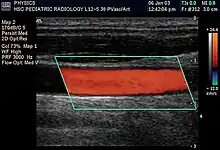

Doppler ultrasonography is medical ultrasonography that employs the Doppler effect to perform imaging of the movement of tissues and body fluids (usually blood),[1][2] and their relative velocity to the probe. By calculating the frequency shift of a particular sample volume, for example, flow in an artery or a jet of blood flow over a heart valve, its speed and direction can be determined and visualized.

Duplex ultrasonography sometimes refers to Doppler ultrasonography or spectral Doppler ultrasonography.[3] Doppler ultrasonography consists of two components: brightness mode (B-mode) showing anatomy of the organs, and Doppler mode (showing blood flow) superimposed on the B-mode. Meanwhile, spectral Doppler ultrasonography consists of three components: B-mode, Doppler mode, and spectral waveform displayed at the lower half of the image. Therefore, "duplex ultrasonography" is a misnomer for spectral Doppler ultrasonography, and more exact name should be "triplex ultrasonography".[3]

Colour Doppler shows the direction of the blood flow in red or blue (either towards or away from the transducer). Meanwhile, spectral Doppler not only shows the direction of blood flow, it also shows the phases (pulsatility) and acceleration of the blood flow. Any sudden changes in direction of blood flow produces audible sounds on the ultrasound machine.[3]

In spectral Doppler, the y-axis shows the direction and velocity of the flow. Meanwhile, the x-axis (as known as "baseline") shows the flow over time. The gradient at any point on the waveform would therefore shows the acceleration of the flow. In "antegrade" flow, the blood flows according to the normal flow within the circulatory system (e.g. veins flow towards the heart while arteries flows away from the heart). In "retrograde" flow, the flow would reverse (e.g. veins flow away from heart or arteries flow towards the heart). However, "retrograde" flow can be both abnormal or normal. For example, in portal hypertension, there is an abnormal portal venous flow where it flows away from the liver (hepatofugal flow) instead of the normal flow towards liver (hepatopetal flow). In jugular venous pressure waveform of the internal jugular vein, the retrograde "a" waveform is a normal flow due to right atrium contraction. Both antegrade or retrograde flow can be either towards or away from the probe transducer, depending on the position of the probe relative to the blood flow. Blood flow toward the transducer would appear above the baseline while blood flows away from the transducer will appear below the baseline. Waveform of the flow can be classified as: pulsatile (as in arteries), phasic (as in veins), non-phasic (as in diseased veins), and aphasic (no flow). Spectral broadening (thickness of the waveform) increases from large vessels (plug flow) to medium vessels (laminar flow) to small/stenotic/diseased vessels (turbulent flow) due to a larger variety of blood with different ranges of velocities in those with turbulent flow.[3]